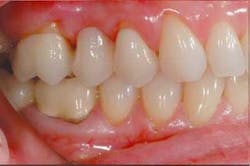

At the framework seating appointment, the patient had only minimum sensitivity and chose not to be anesthetized. The temporary bridge was removed and the final Lava All-Ceramic System bridge was tried-in with warm water. The interproximal contacts were checked for tight or open contacts. The abutment preparation margins were checked with a 10X power surgical microscope and an explorer for any gaps or overhangs. The pontic was checked for tight tissue adaptation and the occlusion checked for even centric stops in the fossa and on marginal ridges. It was determined that there were no working or balancing interferences and no teeth out of occlusion on the bridge.

The bridge was seated and all of the excess cement was removed with the BendaBrush Microfine. (To ensure as easy a cleanup as possible with 3M ESPE RelyX Unicem Self-Adhesive Universal Resin Cement, be sure to remove all of the cement from the margins before it sets, because it bonds to any exposed enamel or dentin and can become difficult to remove. RelyX Unicem cement is a dual-curing cement that sets automatically in five minutes. It does not require any additional light-curing.) After cementation, the bridge and adjacent teeth were inspected for excess resin. The occlusion was confirmed before the patient was dismissed.